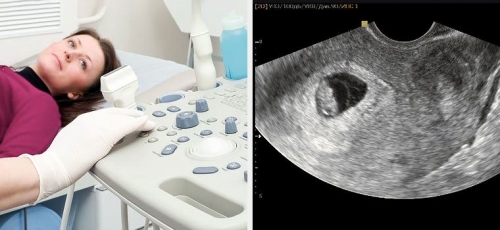

Диагностика миомы матки перед проведением экстракорпорального оплодотворения (ЭКО) является важным этапом, так как наличие миомы может существенно повлиять на успех процедуры и здоровье женщины. Существует несколько методов, которые позволяют выявить миому и оценить её размеры, локализацию и влияние на репродуктивную функцию.

1. Ультразвуковое исследование (УЗИ)

УЗИ является одним из самых распространённых и доступных методов диагностики миомы. С помощью трансвагинального или трансабдоминального УЗИ врач может визуализировать миоматозные узлы, определить их размеры и расположение. Этот метод позволяет также оценить состояние эндометрия и наличие других возможных патологии, которые могут повлиять на успешность ЭКО.